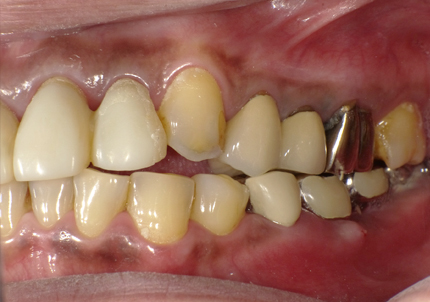

患者:Y.S 様

初診日 :2018年10月

主訴 :上顎前歯部審美障害、臼歯部補綴治療

1.初診時口腔内写真(2018年10月)